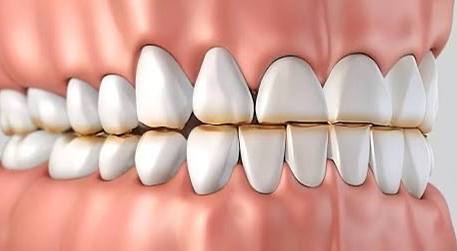

Precision in dentistry is determined not only by the clinician’s experience, but also by the level of visual control over the working field during treatment. Within the clinical approach of